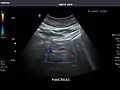

Gallbladder

Gallbladder: No stones, wall thickening, or pericholecystic fluid.

Common Bile Duct: Nondilated measuring 1.3 mm at the level of the porta hepatis.